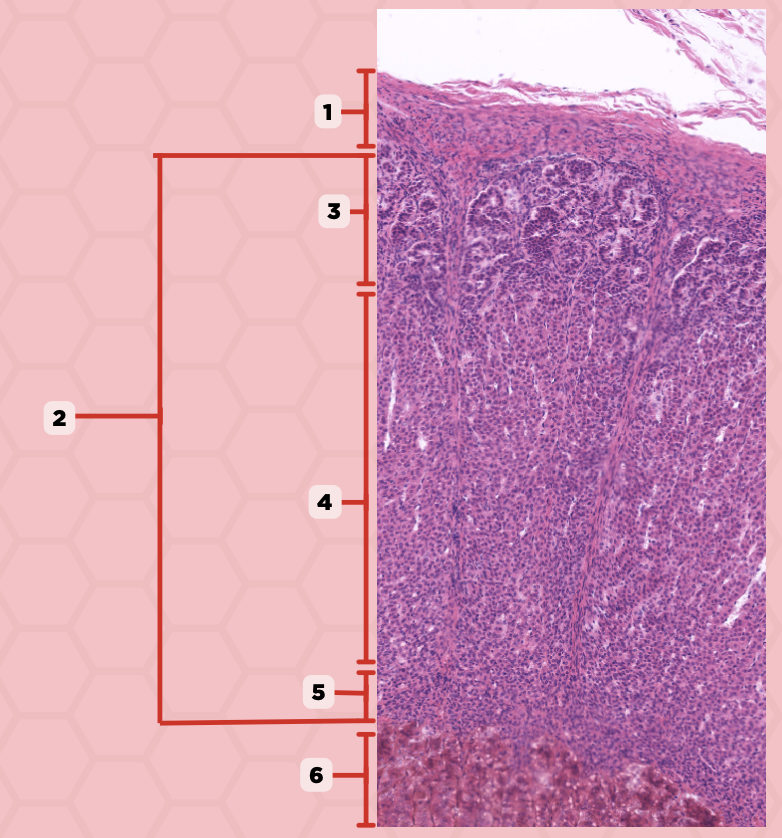

Parathyroid

Identify the specimen.

Chief Cells

Identify the specimen labeled as 1.

Oxyphil Cells

Identify the specimen labeled as 2.

Adipocytes

Identify the specimen labeled as 3.

Capillaries

Identify the specimen labeled as 4.

Newborns

Pointer #2 is hardly present in the parathyroid glands of _____.